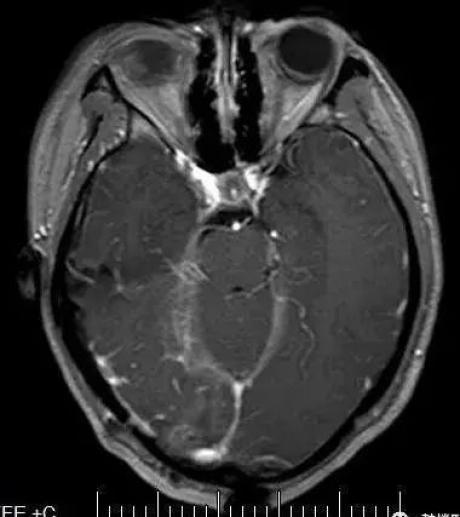

这次的磁共振显示,之前右侧额叶的异常信号虽然减轻了,但是,在同侧的后脑勺部位出现了一个更大的异常信号影,病灶呈现多个不规则的圆圈影,像极了盘绕的蚯蚓!同时,小易的血清寄生虫检查发现了裂头蚴抗原阳性,提示裂头蚴感染可能。

取出虫子后,杭春华主任继续检查虫子周围的脑组织有没有损坏,在仔细清理完被虫子“啃食”的坏死脑组织后关颅,结束了手术。术后小易恢复良好,术后第一天复查磁共振显示虫子已被完全清除,仅有部分水肿待吸收。